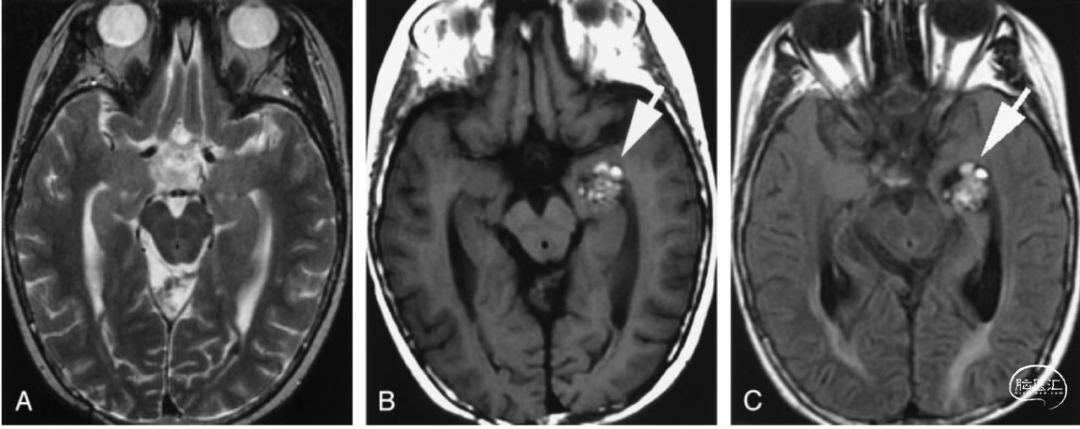

4. 年轻的脑干出血

30岁以下脑干出血挺少见的,得高度怀疑是不是血管出了问题;例如有没有并发海绵状血管瘤,或者发育性静脉畸形?

复查核磁超级重要,这事儿可不能马虎。就算康复得再好,定期去看看医生也是必须的;随访核磁检查能发现的、那些藏着的血管畸形,对预防再出血有大帮助。